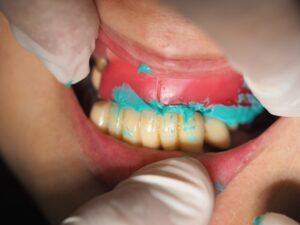

4本のインプラントのデンタル撮影。全て問題なし。ろー堤の印象。

9月12日

ろー提での顎の高さの確認。BTは初診時のスキャンデータでご本人の最初の顎位も確認。その後、アバットメント装着、テック装着。